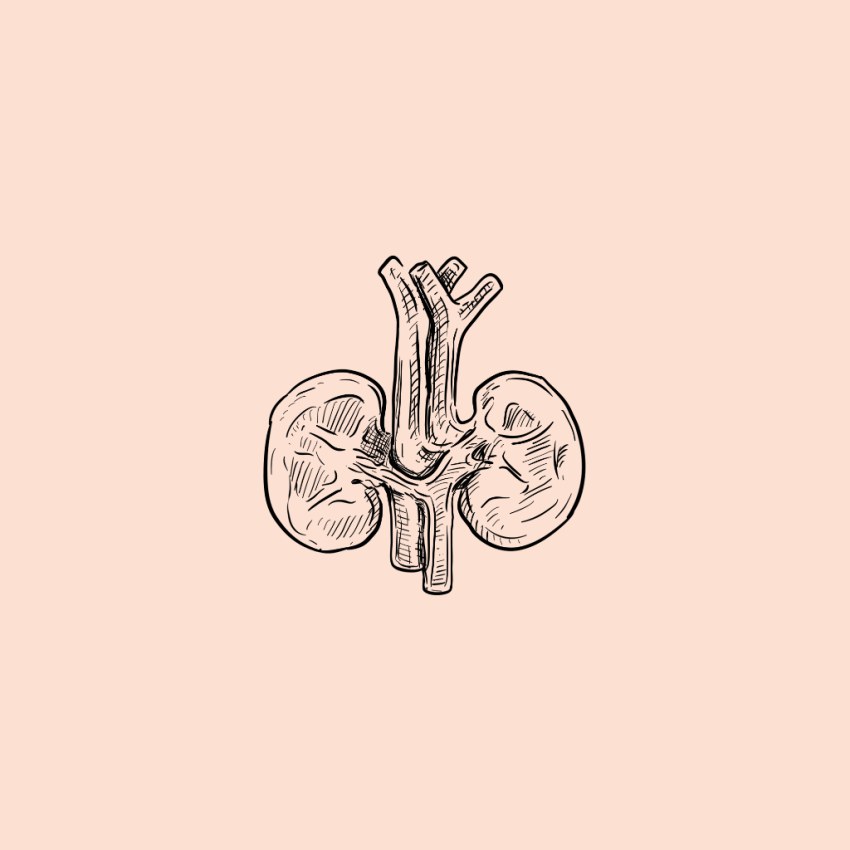

کلیهها در همایستایی نقش اساسی دارند. حفظ تعادل آب، اسید ــ باز، یونها و نیز دفع مواد سمی و مواد زائد نیتروژندار، از جمله وظایف کلیهاند.

حفظ همایستایی بدن فقط برعهده کلیه نیست، اما کلیهها نقش اساسی در آن دارند.

مواد دفعی بدن ما از طریق ساختارهایی مثل کلیه، شش، پوست و لولهی گوارش دفع میشود.

کلیهها

ساختار بیرونی کلیه و حفاظت از آن

کلیهها، اندامهایی لوبیایی شکلاند و به تعداد دو عدد در طرفین ستون مهرهها و پشت محوطۀ شکمی قرار دارند. اندازۀ کلیه در فرد بالغ، تقریباً به اندازۀ مشت بستۀ اوست. به علت موقعیت قرارگیری و شکل کبد، کلیۀ راست قدری پایینتر از کلیه چپ واقع است.